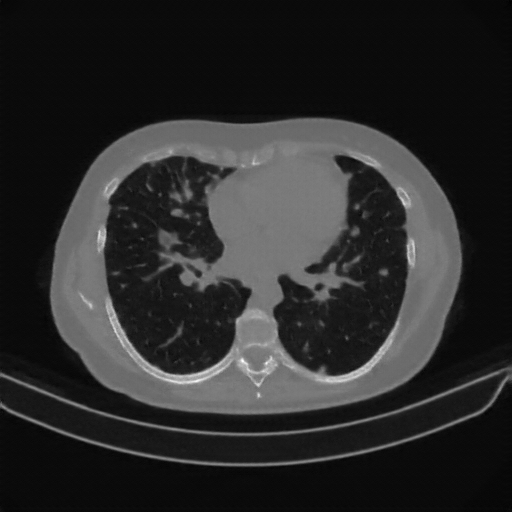

Targeted Slice 70 - Lung Window Analysis (Generated vs Real Venous)

0.752

Lung SSIM

110.9

Lung RMSE

46.5

Lung MAE

Average Lung Window Metrics Across All Slices (133 slices) - Generated vs Real Venous

0.749

Lung SSIM (Avg)

109.7

Lung RMSE (Avg)

44.6

Lung MAE (Avg)

Original NATIVE CT scan (input)

No window - Raw intensity values

Lung window (WL -600, WW 1500 β†’ Low βˆ’1350, High +150)